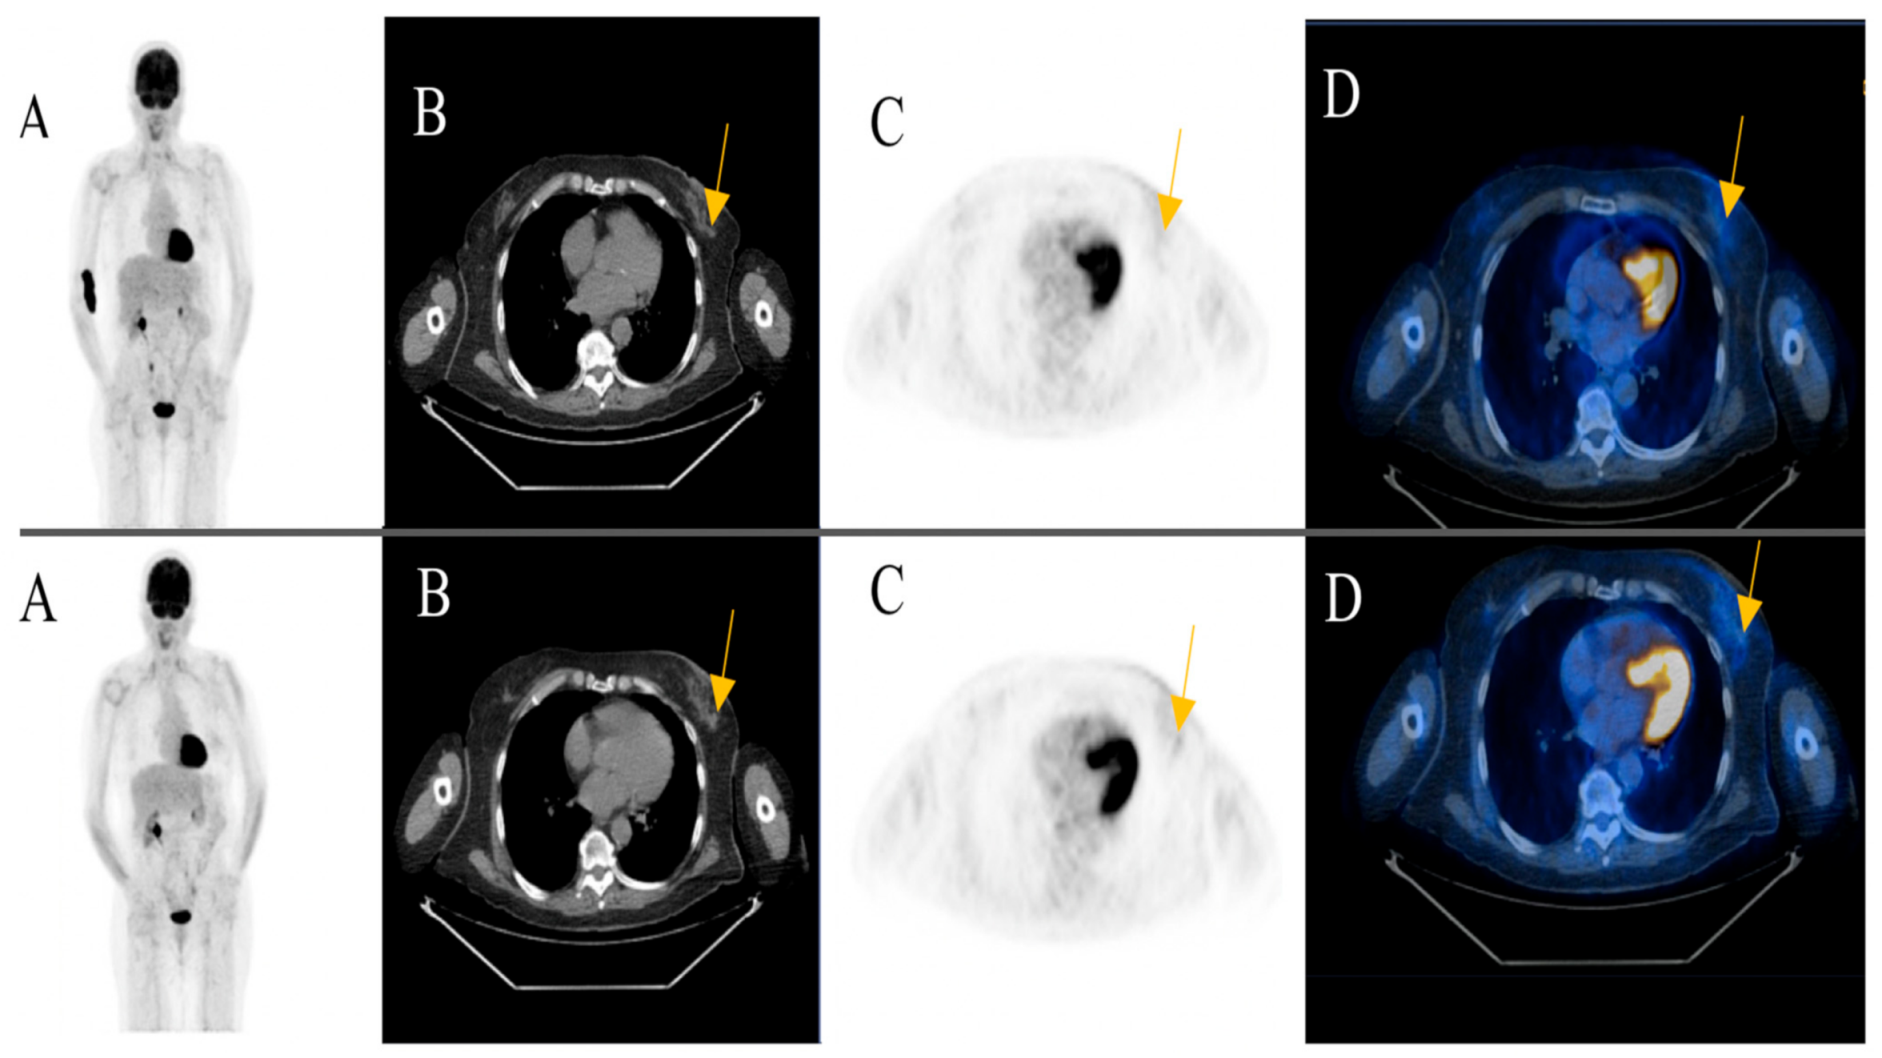

A focal FDG-uptake with wall thickening in the rectosigmoidal colon was also observed in a 72-year-old male patient with metastatic cutaneous melanoma stage IIIC during treatment response assessment. A rectoscopy was subsequently performed based on the recommendation of the reporting physicians. The biopsy revealed a well-differentiated adenocarcinoma of the colon (Figure 4) (Case 2).

Figure 4. A 72-year-old male patient initially with metastatic cutaneous melanoma stage IIIC (T0 N2b M0). (A) Maximum intensity projection (MIP); (B) Computed Tomography (CT) axial of pelvis; (C) Positron Emission Tomography (PET) axial of pelvis; (D) Fused images PET/CT axial of pelvis. First row: FDG-PET/CT performed for extended staging after left axillary lymphadenectomy without evidence of metabolically active melanoma, nodal or distant metastasis. Second row: Follow-up for treatment response assessment under anti-PD1 monotherapy. Three months after treatment initiation, a new metabolically active wall thickening of the rectosigmoidal colon was seen (yellow arrow). A rectoscopy was subsequently recommended for further evaluation. The biopsy revealed a well-differentiated adenocarcinoma of the colon.